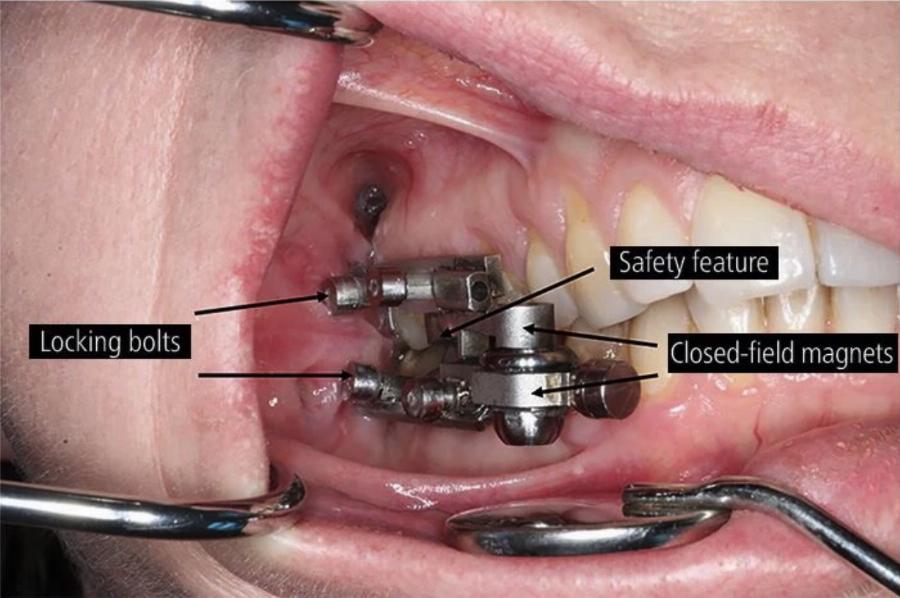

Η συσκευή χρησιμοποιεί μαγνήτες για να εμποδίσει τους ανθρώπους να ανοίξουν το στόμα τους αρκετά ώστε να καταναλώνουν στερεά τρόφιμα .

Αναπτύχθηκε από το Πανεπιστήμιο του Otago στη Νέα Ζηλανδία και επιστήμονες από το Leeds στο Ηνωμένο Βασίλειο για την αντιμετώπιση της παχυσαρκίας και μπορεί να τοποθετηθεί από οδοντίατρους και να χρησιμοποιεί μαγνητικά εξαρτήματα που επί της ουσίας “ασφαλίζουν” το στόμα.

Η συσκευή ονομάζεται DentalSlim Diet Control και επιτρέπει στους χρήστες της να ανοίγουν το στόμα τους σε πλάτος μόνο 2 χιλιοστών.